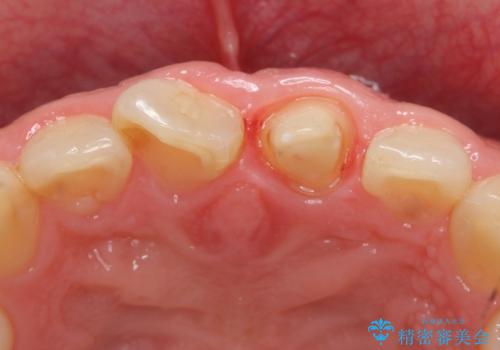

- 前歯の長さが気になるのでセラミックで治療したいといらっしゃった方の症例です。

御希望された再根管治療終了後、オールセラミッククラウンによる補綴を行いました。